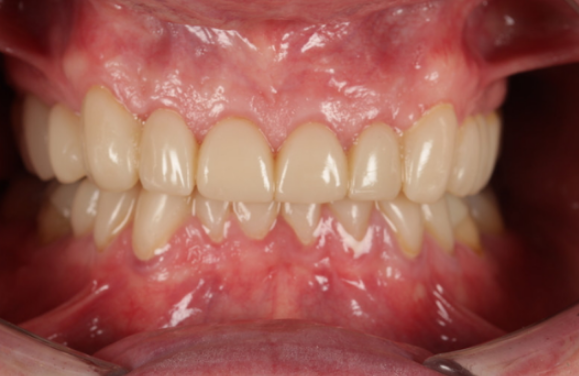

從左到右、從上到下,3D打印技術(shù)幫助減輕了患者的嚴(yán)重牙齒磨損。

最終產(chǎn)品展現(xiàn)了3D打印技術(shù)在牙科領(lǐng)域的強(qiáng)大威力。

患者對改善后的外觀和舒適度立即表示滿意。術(shù)后兩周、一個月、兩個月和三個月的隨訪評估證實,他已很好地適應(yīng)了恢復(fù)后的垂直咬合關(guān)系和新的修復(fù)體。通過保留牙釉質(zhì)并最大限度地減少牙體磨除,這種方法降低了牙髓并發(fā)癥(牙神經(jīng)炎癥或刺激)的風(fēng)險,同時優(yōu)化了患者的舒適度和長期口腔健康。